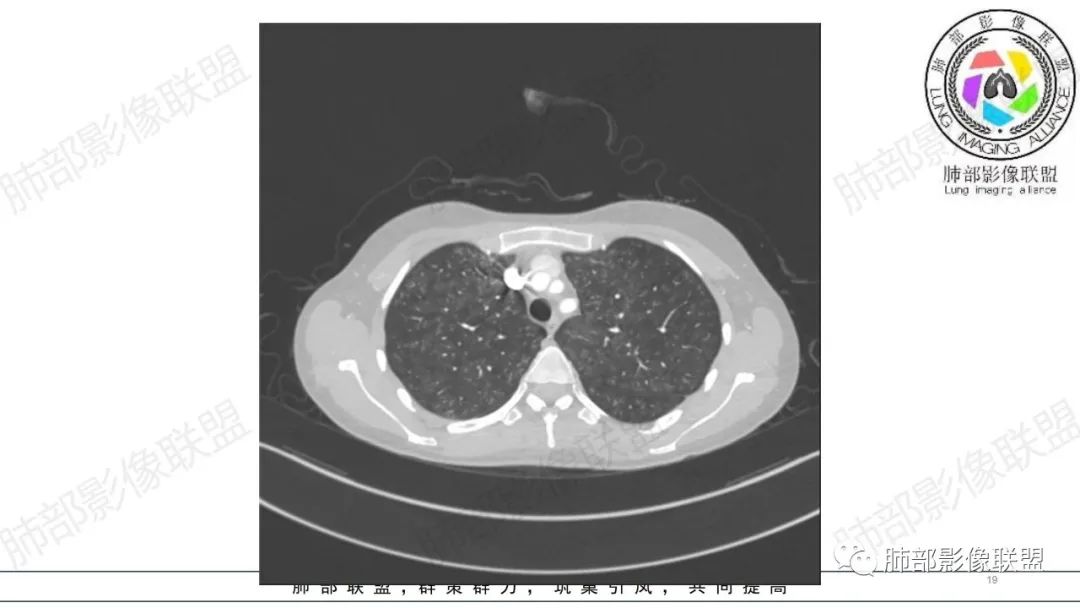

影像资料

34岁女性患者,“哮喘”病史30年,近期有可疑刺激性气体吸入史;因乏力半年,咳嗽、憋气、发热4天就诊;6.1CT提示双肺广泛毛玻璃影及粟粒样结节,胸膜下闲置及血管周闲置,可见树丫征,部分小叶间隔增厚。考虑:1.过敏性肺泡炎,有可疑刺激气体接触史,胸膜下闲置,广泛毛玻璃影,地图样分布,粟粒结节边界模糊,支持过敏性肺泡炎,但糖皮激素治疗效果不佳,且动态复查血常规血红蛋白进行性降低,过敏性肺泡炎 不符合;2.肺含铁血黄素沉积症:患者30“哮喘”病史,可能为肺含铁症状,肺部CT提示双肺弥漫毛玻璃影及粟粒结节影,中下肺明显,肺底部分小叶间隔增厚,近期咳嗽、憋气、发热,血常规血红蛋白进行性下降,考虑肺含铁急性期症状,但临床无咯血症状,肺含铁不典型。综合考虑:肺含铁血黄素沉积症>过敏性肺泡炎。

年轻女性 ,急性喘息发热,肺部影像弥漫磨玻璃密度,部分细小腺泡结节,胸膜下黑线显示,短期复查,病变密度增高,下肺明显,血管周围肺组织累及较少、且逐渐成小叶间隔分布。考虑弥漫肺泡内病变,并经淋巴道转移,下肺比上肺明显,多为免疫细胞功能下肺较强。1.过敏性肺泡炎,有相关病史,三层密度特点、头尾测分布,符合。2 肺泡微石症,多有钙化,且缓慢起病,病程不太符合,放待排。3 吸入相关肺损伤,有病史,疾病演变过程也符合渗出-肉芽肿改变,建议详细询问病史。4 感染性病变,结核?病变气道分布为主,如此弥漫且没有树丫不符合。5.巨细胞病毒,可以磨玻璃 结节 改变,没有免疫缺陷病史。最后考虑吸入所致 1过敏性肺泡炎、吸入性肺损伤 鉴别肺泡微石症。